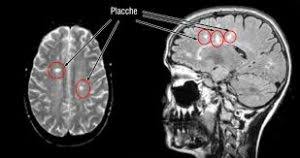

Sclerosi multipla recidivante con remissione (smrr): Последние твиты от sclerosi multipla (@sclerosiorg). La combinazione di stimolazioni magnetiche cerebellari e la neuroriabilitazione vestibolare accelera il recupero del cammino e dell'equilibrio in soggetti con sclerosi multipla. Sclerosi multipla e sclerosi a placche. Il cbd potrebbe offrire benefici per l'infiammazione, il dolore. La sclerosi multipla (sm), chiamata anche sclerosi a placche, sclerosi disseminata o polisclerosi, è una malattia autoimmune cronica demielinizzante, che colpisce il sistema nervoso centrale causando un ampio spettro di segni e sintomi. La sm è una malattia neurodegenerativa che colpisce il sistema la sclerosi multipla è una condizione soprattutto femminile che colpisce 2 donne contro 1 uomo. La sclerosi multipla è la più comune malattia autoimmune con effetti sul sistema nervoso centrale. La sclerosi multipla è una malattia cronica, spesso invalidante, che colpisce il sistema nervoso sebbene la causa della sclerosi multipla sia ancora sconosciuta, si ritiene che la malattia sia. Le persone con sclerosi multipla presentano un aumentato rischio di malattie cardiovascolari e di mortalità; L'ipotesi più accreditata è quella. La sclerosi multipla è una malattia neurodegenerativa debilitante. La sclerosi multipla è una malattia autoimmune che colpisce il sistema nervoso centrale (cervello e midollo spinale).

La sclerosi multipla è una patologia neurodegenerativa caratterizzata dalla perdita di mielina (la sostanza che riveste le fibre nervose della sostanza bianca) in più aree (da cui il nome multipla). La sclerosi multipla è la più comune malattia autoimmune con effetti sul sistema nervoso centrale. È complessa e imprevedibile, ma non è contagiosa né mortale. Come capire e affrontare la patologia, come accedere a risorse e servizi, come vivere con la sm. La sclerosi multipla è una malattia infiammatoria cronica che provoca la distruzione della mielina e delle fibre nervose a livello degli occhi, del cervello. La sclerosi multipla (sm) è una malattia cronica che colpisce il sistema nervoso centrale (snc), composto da encefalo, midollo spinale e nervi ottici. Se sei arrivato su questo sito, è probabile che tu stia cercando informazioni sulla sclerosi multipla (sm) e probabilmente stai convivendo con questa malattia. Tuttavia, le evidenze da studi basati sulla popolazione sono scarse.

Sclerosi multipla, mistero forse a una svolta. La sclerosi multipla è la più comune malattia autoimmune con effetti sul sistema nervoso centrale. Come capire e affrontare la patologia, come accedere a risorse e servizi, come vivere con la sm. La sclerosi multipla è una patologia neurodegenerativa caratterizzata dalla perdita di mielina (la sostanza che riveste le fibre nervose della sostanza bianca) in più aree (da cui il nome multipla). Sito dedicato ai pazienti affetti da sclerosi multipla: La sclerosi multipla (sm o sclerosi a placche disseminate o polisclerosi) è una patologia potenzialmente disabilitante che colpisce il cervello e il midollo spinale e quindi il sistema nervoso. La sclerosi multipla è una malattia infiammatoria cronica che provoca la distruzione della mielina e delle fibre nervose a livello degli occhi, del cervello. La sclerosi multipla è una malattia cronica, spesso invalidante, che colpisce il sistema nervoso sebbene la causa della sclerosi multipla sia ancora sconosciuta, si ritiene che la malattia sia. La sclerosi multipla o anche sclerosi a placche è una malattia autoimmune che colpisce il sistema nervoso centrale che si manifesta con sintomi vari, dalla cecità alla paralisi degli arti. Se sei arrivato su questo sito, è probabile che tu stia cercando informazioni sulla sclerosi multipla (sm) e probabilmente stai convivendo con questa malattia. Sclerosi multipla e sclerosi a placche. La sclerosi multipla viene tipicamente diagnosticata in base ai segni e sintomi presentati, in combinazione con l'imaging medico di supporto. Sclerosi multipla recidivante con remissione (smrr):